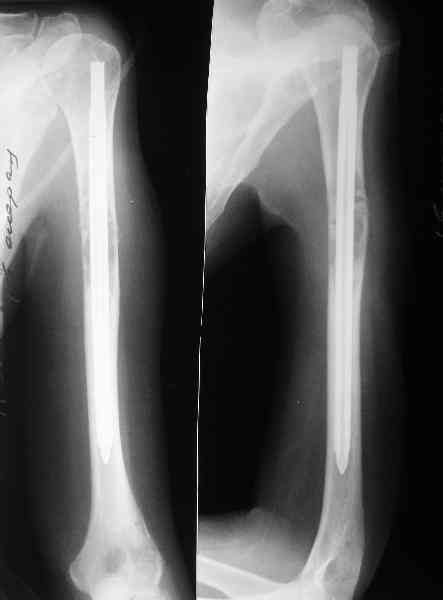

Сегодня сделали, Fixion диаметром 7,4 мм. Обе пперации продолжались по

7 мин. Картинки в приложении. Наркоз был диприваном, на спонтанном

Гвоздик 7,4 расширяется до 11 мм. Не маловато ли, судя по снимкам?